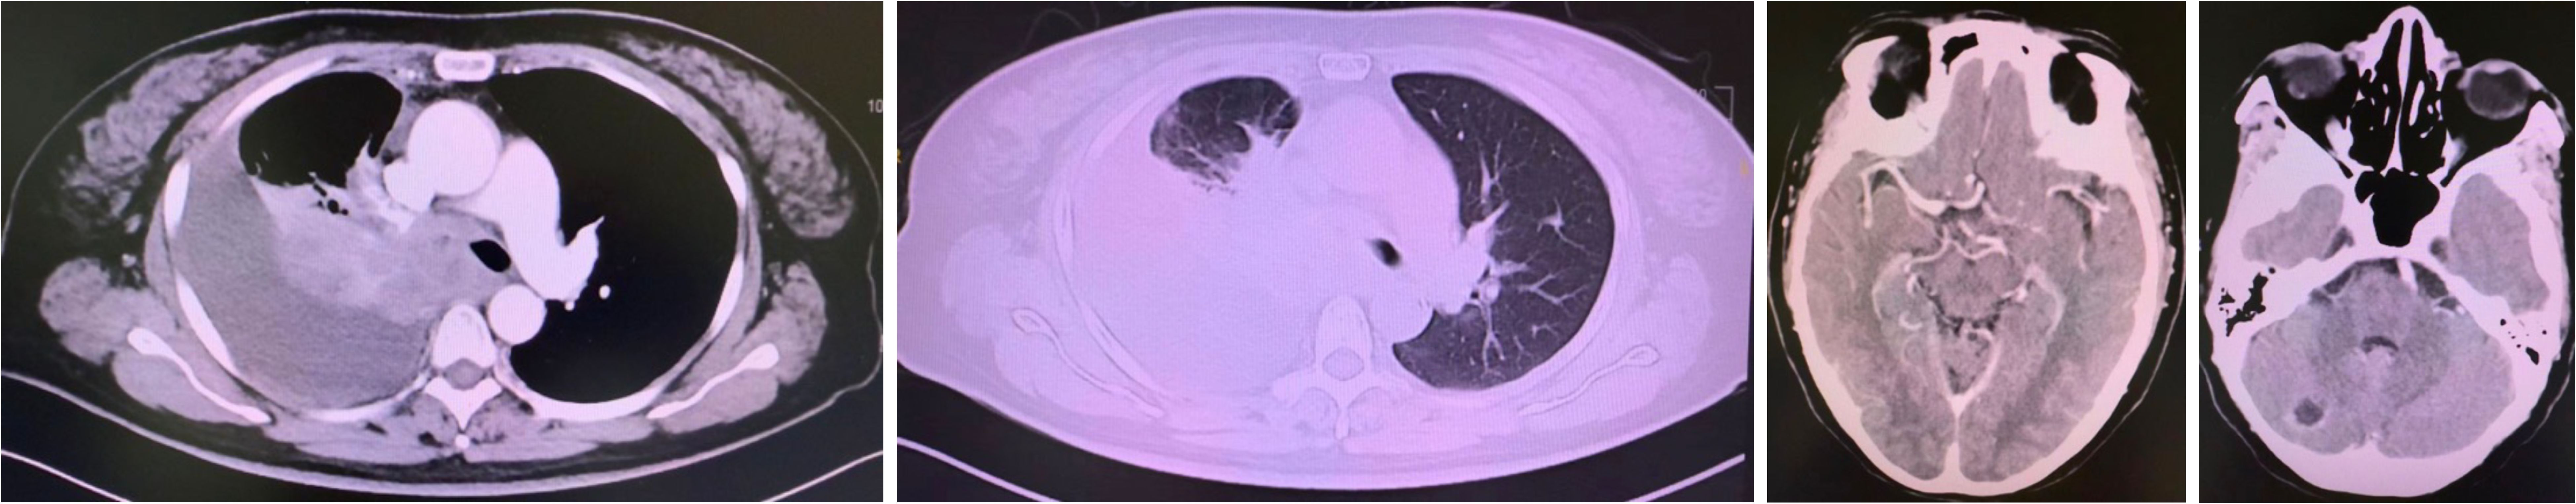

A CT-guided biopsy revealed transformation to small-cell lung cancer with maintained neuroendocrine marker expression. Second-line therapy with etoposide (100 mg/m² days 1-3) and cisplatin (75 mg/m² day 1) was administered for four cycles (9). CT scans showed that the lung lesions had significantly shrunk. (Figure 2) The patient subsequently received consolidative radiotherapy: whole-brain radiotherapy (39 Gy in 13 fractions) followed by intensity-modulated radiotherapy to the primary lung tumor (45 Gy in 30 fractions) (10, 11). Histological analysis from a re-biopsy of the progressive chest lesion revealed small cell cancer transformation and tested positive for neuroendocrine markers, including synaptophysin, chromogranin A, and CD56. Tissue and blood samples were subjected to next-generation sequencing (NGS), which revealed an EGFR exon 21 L858R deletion. In March 2021, PET/CT and brain MRI revealed new metastatic lesions in the pleura and liver capsule, with an increase in multiple metastatic tumors in the brain. (Figure 3) Serum tumor markers showed elevated carcinoembryonic antigen (CEA) (8.1 ng/mL) while NSE remained normal (11.3 ng/mL). Following disease progression, a third biopsy of the chest mass was performed, but no tumor tissue was detected. Circulating tumor DNA (ctDNA) from peripheral blood revealed an EGFR exon 21 L858R deletion. We considered that the recurrent focus might be adenocarcinoma of the lung. Plasma ctDNA analysis confirmed persistence of EGFR L858R mutation without additional resistance alterations. Third-line therapy (from April 20 to July 21, 2021) with paclitaxel (200 mg/m²), carboplatin (AUC 5), and bevacizumab (15 mg/kg) was administered every three weeks (12). After four cycles, CEA decreased to 3.9 ng/mL, and CT imaging showed a partial response (Figure 4). Treatment was complicated by grade 2 epistaxis, leading to bevacizumab discontinuation. The patient was switched to maintenance therapy with aumolertinib (110 mg daily) combined with anlotinib (12 mg daily, days 1–14 every 21 days) (13, 14). Follow-up assessments at 2, 6, 10, and 14 months showed sustained clinical and radiographic stability. The patient ultimately died due to progressive brain metastases in November 2022, with an overall survival of 48 months. The course of treatment is presented in Figure 5.

Figure 4

Three medical imaging scans are shown. The first two scans are transverse chest CT images displaying a large mass in the thoracic cavity, with differing brightness levels. The third scan depicts an axial MRI of the brain, revealing detailed structural features. Each image highlights specific anatomical areas for diagnostic purposes.

Figure 4. Partial response after paclitaxel, carboplatin, and bevacizumab #4.